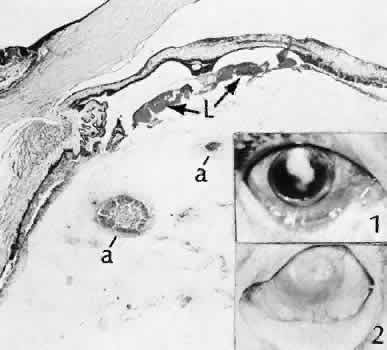

Rupture of the posterior lens capsule (Fig. 28) increases the risk of vitreous loss and limits options for the implantation of an intraocular lens. Retention of lens capsular tissue or vitreous in the wound (Fig. 29) will significantly delay the wound healing process. Vitreous loss leads to an increased incidence of iris prolapse, bullous keratopathy, epithelial downgrowth, stromal overgrowth, wound infection and endophthalmitis, updrawn or misshapen pupil, vitreous bands, postoperative flat anterior chamber, secondary glaucoma, retinal detachment, cystoid macular edema, optic disc edema, vitreousopacities, vitreous hemorrhage, and other sight-threatening consequences.92

Fig. 28. A case of lens capsular rupture during intracapsular cataract extraction. On postoperative day 1 (inset 1), there was considerable retention of lens capsular material nearly obscuring the anterior chamber. By postoperative day 14 (inset 2), considerable clearing of debris has occurred. At 2 months following surgery (inset 3), the anterior chamber was nearly clear. The clearing of the debris was through the action of macrophages ingesting the cortical debris and exiting the eye through the trabecular apparatus. Macrophages filled with lens cortical material from a different case are seen in the main figure. (Periodic acid-Schiff stain; × 700.) (Yanoff M, Scheie HG: Cytology of human lens aspirate. Its relationship to phacolytic glaucoma and phacoanaphylactic endophthalmitis. Arch Ophthalmol 80:166–170, 1968.)